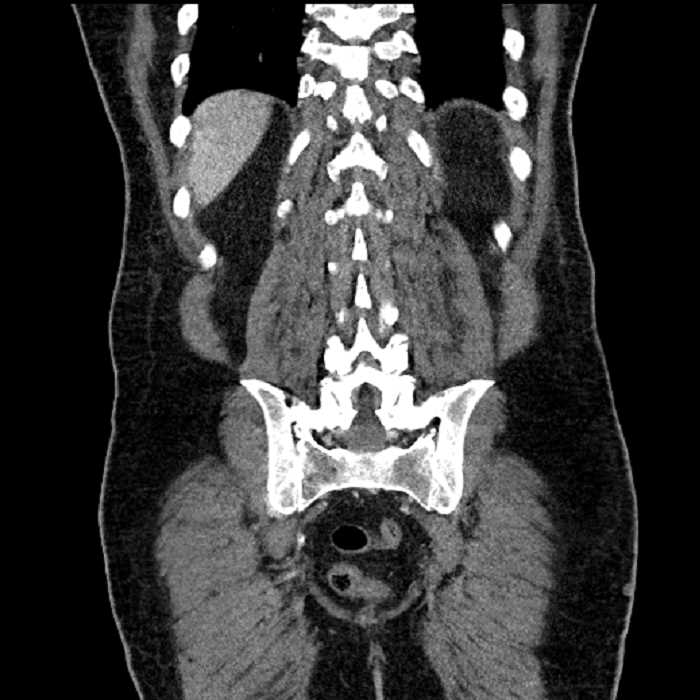

• Large fluid density structure in hepatic segments 7 and 8 measuring 10 x 7 x 7 cm with internal septation and circumferential ill-defined low density compatible with edema

• Peripherally enhancing subcapsular collections along the anterior margin of the left hepatic lobe measuring 3 x 1 cm and 2 x 1 cm

• Clearly marginated fluid density structure in segment 7 and several other scattered tiny hypodensities, which likely represent cysts

• Hepatic abscess

Acute sigmoid diverticulitis complicated by a small contained perforation and a large abscess in the right hepatic lobe. Additional small subcapsular abscesses along the anterior margin of the left hepatic lobe.

• The classic CT imaging appearance is a double target sign with internal low density surrounded by an internal enhancing rim (capsule) and a low density external rim (edema)

Hepatic abscess showing the double target sign with low density internally surrounded by a thin inner enhancing rim (red arrow) and ill-defined outer low density rim (yellow arrow). Blue arrow indicates an internal septation. Red arrows: additional smaller subcapsular abscesses. Red arrow: focal contained perforation associated with diverticulitis.